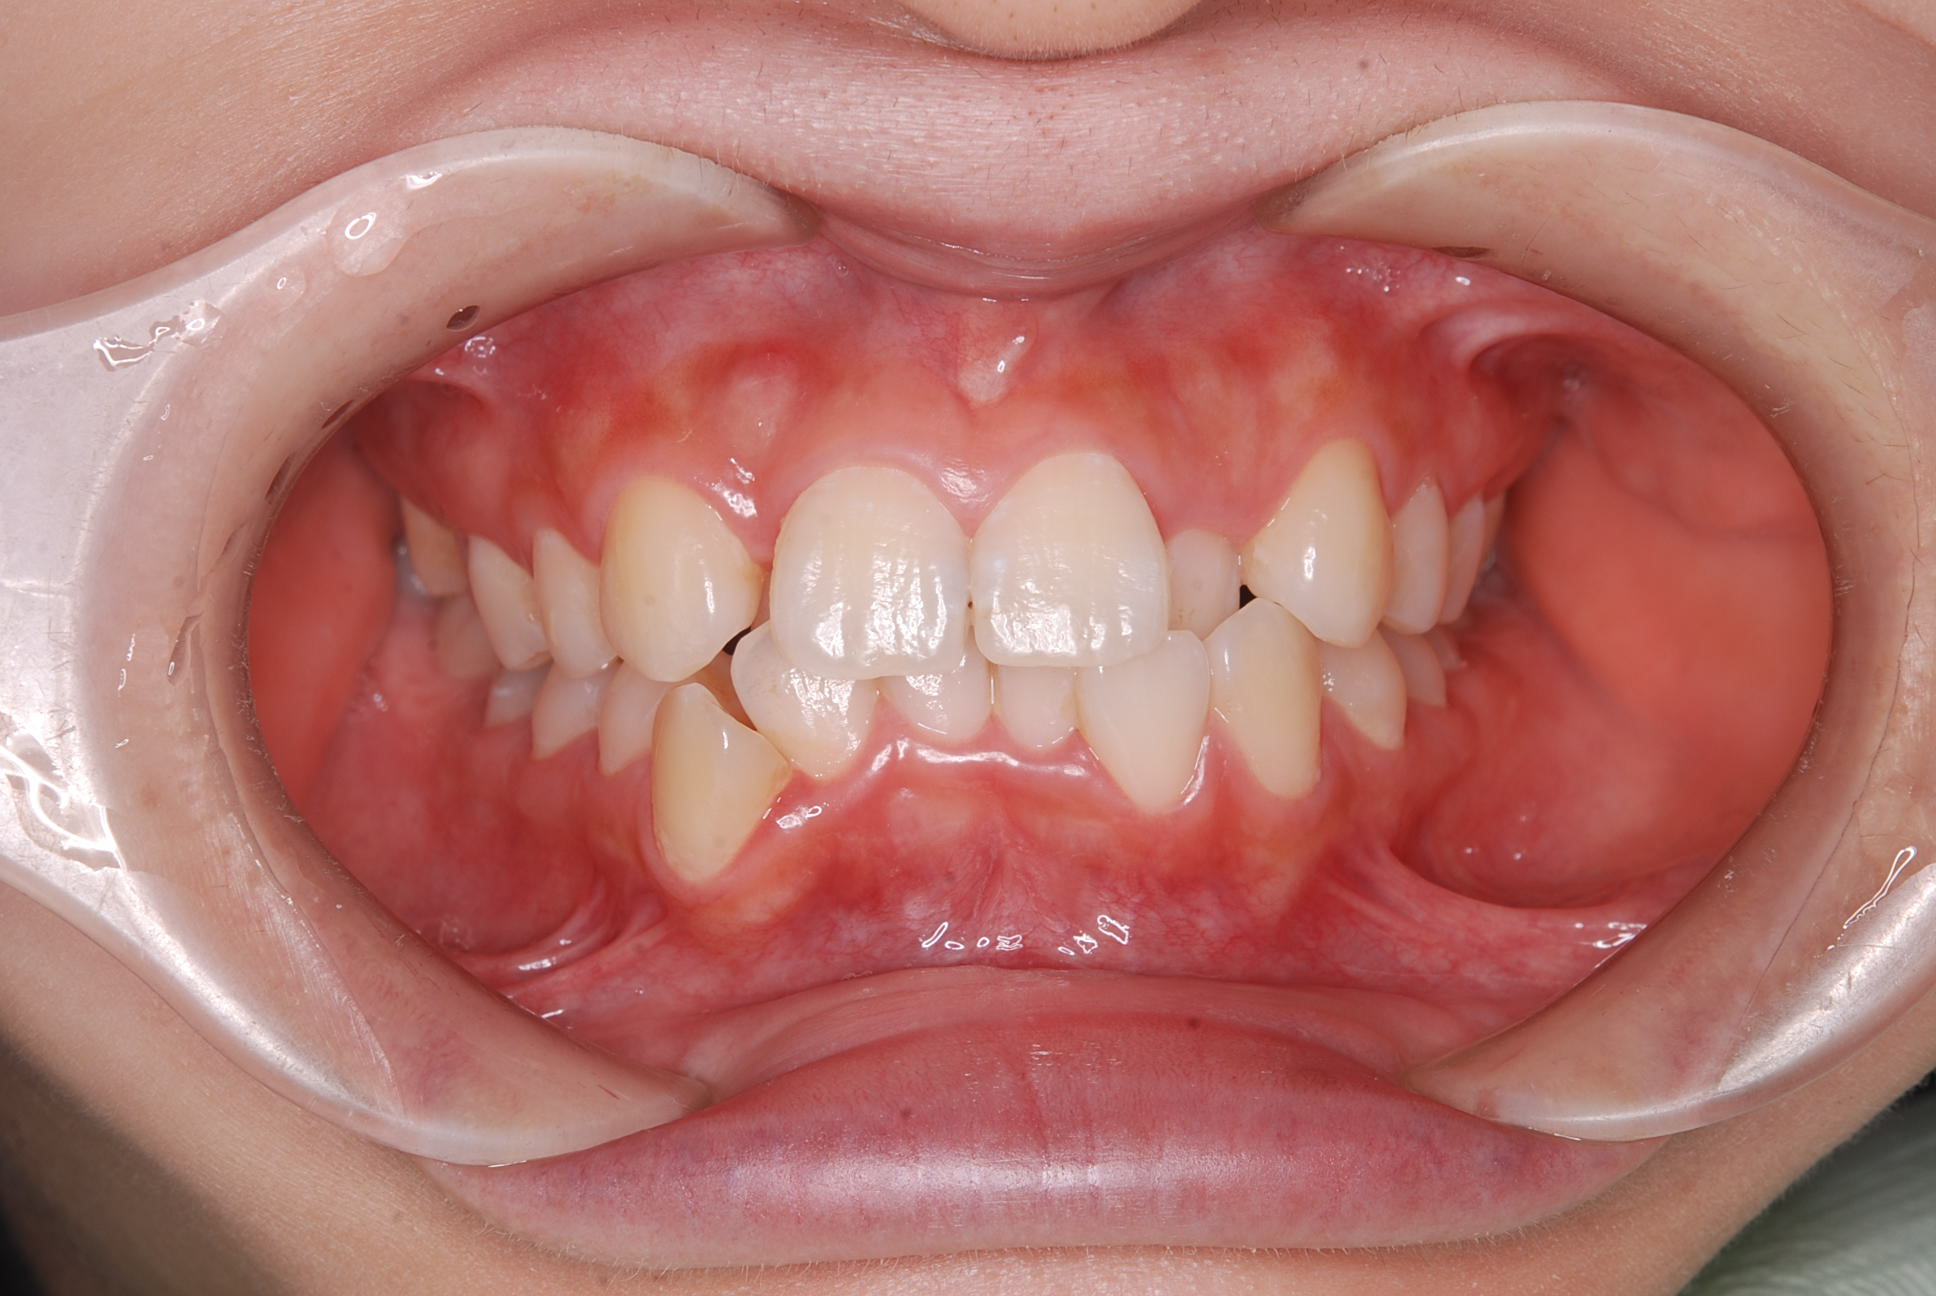

歯並びのガタガタ

上下顎に叢生(歯並びのガタガタ) と部分的な反対咬合を認める。

前歯の反対咬合は顎位の変化を示す兆候であるため、矯正治療と並行して顎関節症に対するケアが必要。